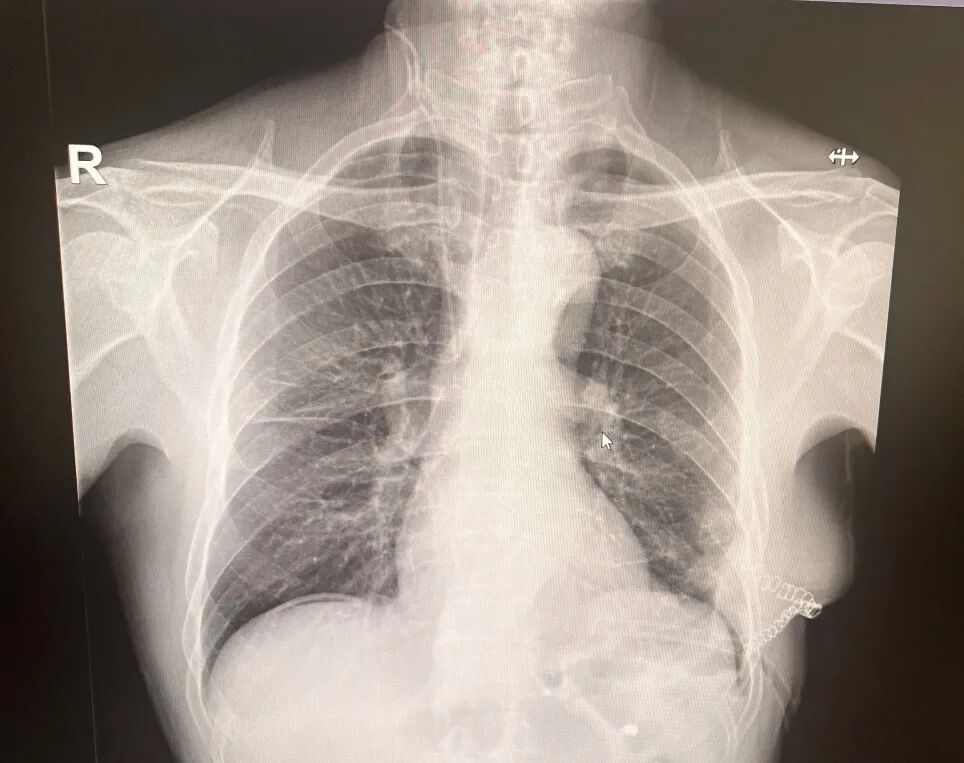

術(shù)前影像

輾轉(zhuǎn)來到市二院胸外科,孫振教授在細致追問病史時,捕捉到一個關(guān)鍵細節(jié):10年前,患者胸腹部曾被刀刺傷,當時僅做了外部縫合,未深入排查內(nèi)部損傷。這一信息引起了孫振教授的高度警覺——很多陳舊性胸腹外傷雖表面愈合,卻可能遺留膈肌破裂的隱患,并隨時間推移發(fā)展為創(chuàng)傷性膈疝。腹部增強CT結(jié)果證實了這一判斷。